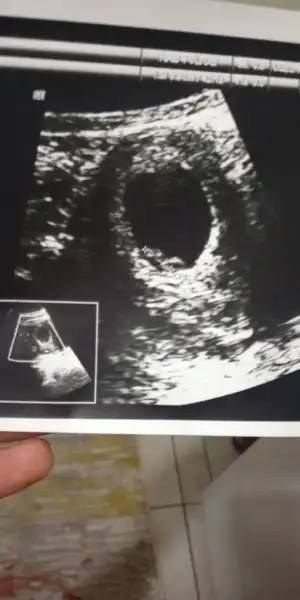

Kizlar bi arkdsimin bebisi bu 🤗 sizce cinsiyeti nedir belli mi

• IMG-20190909-WA0046.webp

IMG-20190909-WA0046.webp

22 KB · Görüntüleme: 62